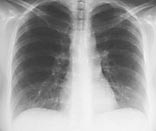

Pasient 2. 29 år gammel tidligere frisk kvinne innlagt med tre dagers sykehistorie. Hun hadde influensasymptomer med muskelverk, ryggsmerter, hodepine og temperatur opp i 40,8 ˚C. Hun var tilsett på poliklinikken dagen i forveien, hun klaget da over tørrhoste. Røntgen thorax var negativt (fig 1) CRP var 178 mg/l, trombocytter 78 _ 109/l og leukocytter 2,5 _ 109/l. Ved innleggelse hadde hun respirasjonsfrekvens på 30, puls 130, temperatur 39,1 ˚C, og røntgen thorax viste nå bilaterale konfluerende fortetninger (fig 2). CRP var steget til 248 ml/l, trombocytter var falt til 60 _ 109/l, det var lett forhøyede transaminaser, normalt kreatininnivå og fibrin degradasjonsprodukter (FDP-DD) var 8,0. Tilstanden ble nå oppfattet som en pneumoni eller sepsis med sjokklungeutvikling. Hun ble satt på behandling med høydose penicillin-G, netilmycin og erytromycin.

Pneumokokker er det viktigste agens ved alvorlig pneumoni ervervet utenfor sykehus (2). Pneumokokker kan også hos tidligere friske gi et akutt alvorlig sykdomsbilde med respirasjonssvikt. Røntgenologisk finner man ved sykdomsdebut oftest infiltrat som involverer et segment eller en hel lungelapp (3). Ved kompliserende sjokklungeutvikling vil diffuse bilaterale infiltrater kunne utvikles senere i forløpet. Hos våre to pasienter var det imidlertid en utvikling fra nær normalt røntgen thorax til svære bilaterale infiltrater i løpet av 36 timer.